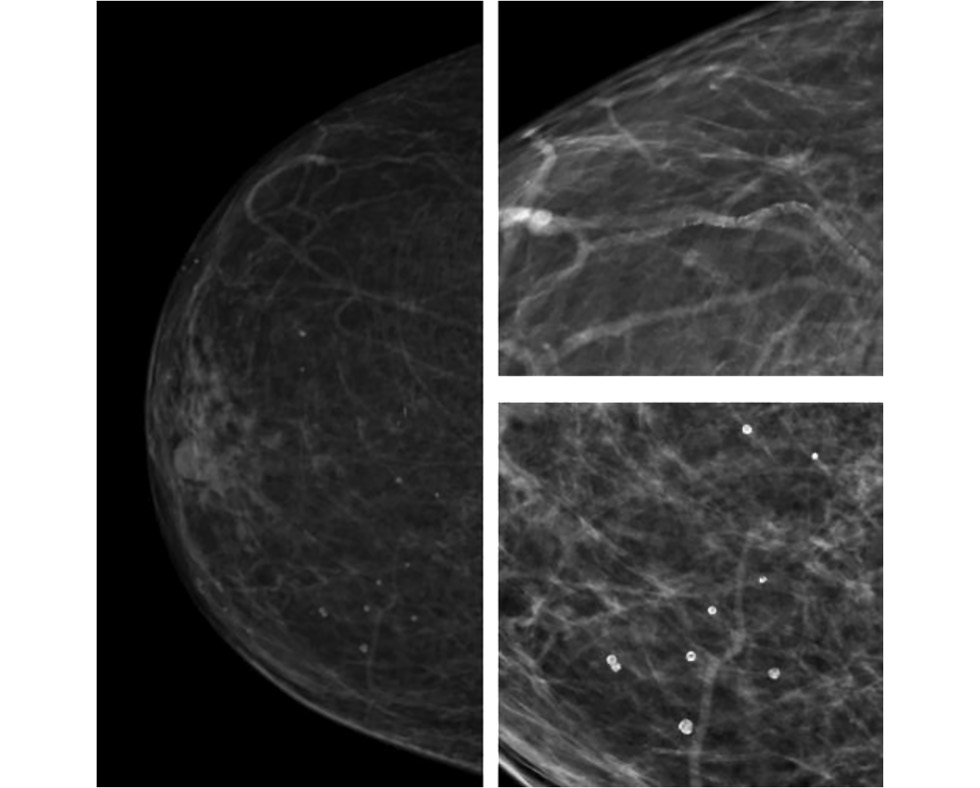

Radiographic markers of cardiovascular risk based on digital mammograms: a cross-sectional study

Abstract

BACKGROUND: Studies have demonstrated an association between cardiovascular risk and mammographic density and breast arterial calcification. However, their combined impact remains poorly understood.

AIM: This study aimed to evaluate the correlation between mammographic density, breast artery calcification, and cardiovascular risk category in asymptomatic women aged ≥40 years.

METHODS: This retrospective, single-center, selective study included women who underwent preventive screening mammography at the University Clinic of Lomonosov Moscow State University between 2019 and 2023. The Systematic Coronary Risk Evaluation 2 was used to determine cardiovascular risk categories. A radiologist evaluated mammograms at a workstation to obtain data on mammographic density and glandular calcifications. The data were analyzed using a machine learning technique called Uniform Manifold Approximation and Projection. Univariate logistic regression was employed to calculate odds ratios and 95% confidence intervals. The reference group included mammograms showing high breast density and no calcifications. The odds ratio for each selected group is presented relative to the reference. The contingency tables were assessed using Pearson’s chi-squared (χ2) test. The significance level for all tested hypotheses was set at 0.05.

RESULTS: The mammograms of 1030 women aged 40–89 years were evaluated. Based on the study results, eight groups (G7–G0) were formed, depending on combinations of the following criteria: high or low glandular density, presence or absence of vascular and nonvascular calcification, and extent of calcification. Women with low mammographic density and vascular calcifications in more than one quadrant were found to have a >75% likelihood of high or extremely high cardiovascular risk. The probability exceeded 90% for a combination of vascular and nonvascular calcifications in two or more quadrants.

CONCLUSION: A correlation was found between calcifications, mammographic density, and cardiovascular risk category.